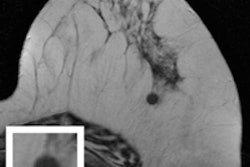

CAD for DBT

Finally, visit our Advanced Visualization Community to learn about how a group from the University of Michigan used computer-aided detection (CAD) to improve the performance of digital breast tomosynthesis (DBT) while reducing radiation dose.

What's unique is that they applied two different CAD algorithms, which enabled them to use a special DBT protocol with a smaller image acquisition arc that collects 3D mammography images with half the normal dose. Find out how they did it by clicking here, or visit the community at av.auntminnie.com.